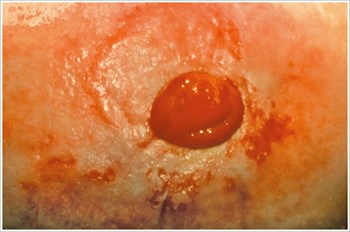

Basınç Ülseri

Açıklama/Nedenler:

Stoma kemeri, dar giysiler, sert ön yüz, peristomal fıtık veya işle ilgili alışkanlıklardan kaynaklanan aşırı basıncın neden olduğu peristomal bölgede ülser.

Belirtileri:

• Ağrı

• Düzensiz şekilli ülser

• Torba sızıntısı

• Azaltılmış kullanım süresi